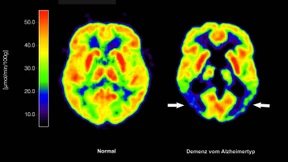

In einigen Ländern wird Alzheimer schon sehr früh mithilfe von verschiedenen Tests erkannt. Die Krankheit kann dann mit neuen Wirkstoffen behandelt werden. In Deutschland geht das noch nicht. Woran das liegt.